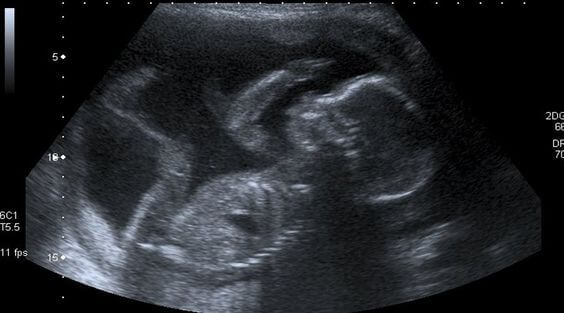

Só uma mãe mulher sabe a emoção de seu primeiro ultrassom, quando não consegue conter as lágrimas de emoção ao ouvir o coração de seu filho batendo rapidamente. Assim também bate o seu próprio coração quando transborda de alegria com esse primeiro contato.

Essa mamãe também sabe que no presente momento e por pelo menos nove meses deverá se contentar com imagens proporcionadas pelos ultrassons. Elas terão de ser o suficientes para poder dar um rostinho ao seu filho, e complementarão a sensação de sentir os seus movimentos sutis que pouco a pouco se tornam mais ativos.